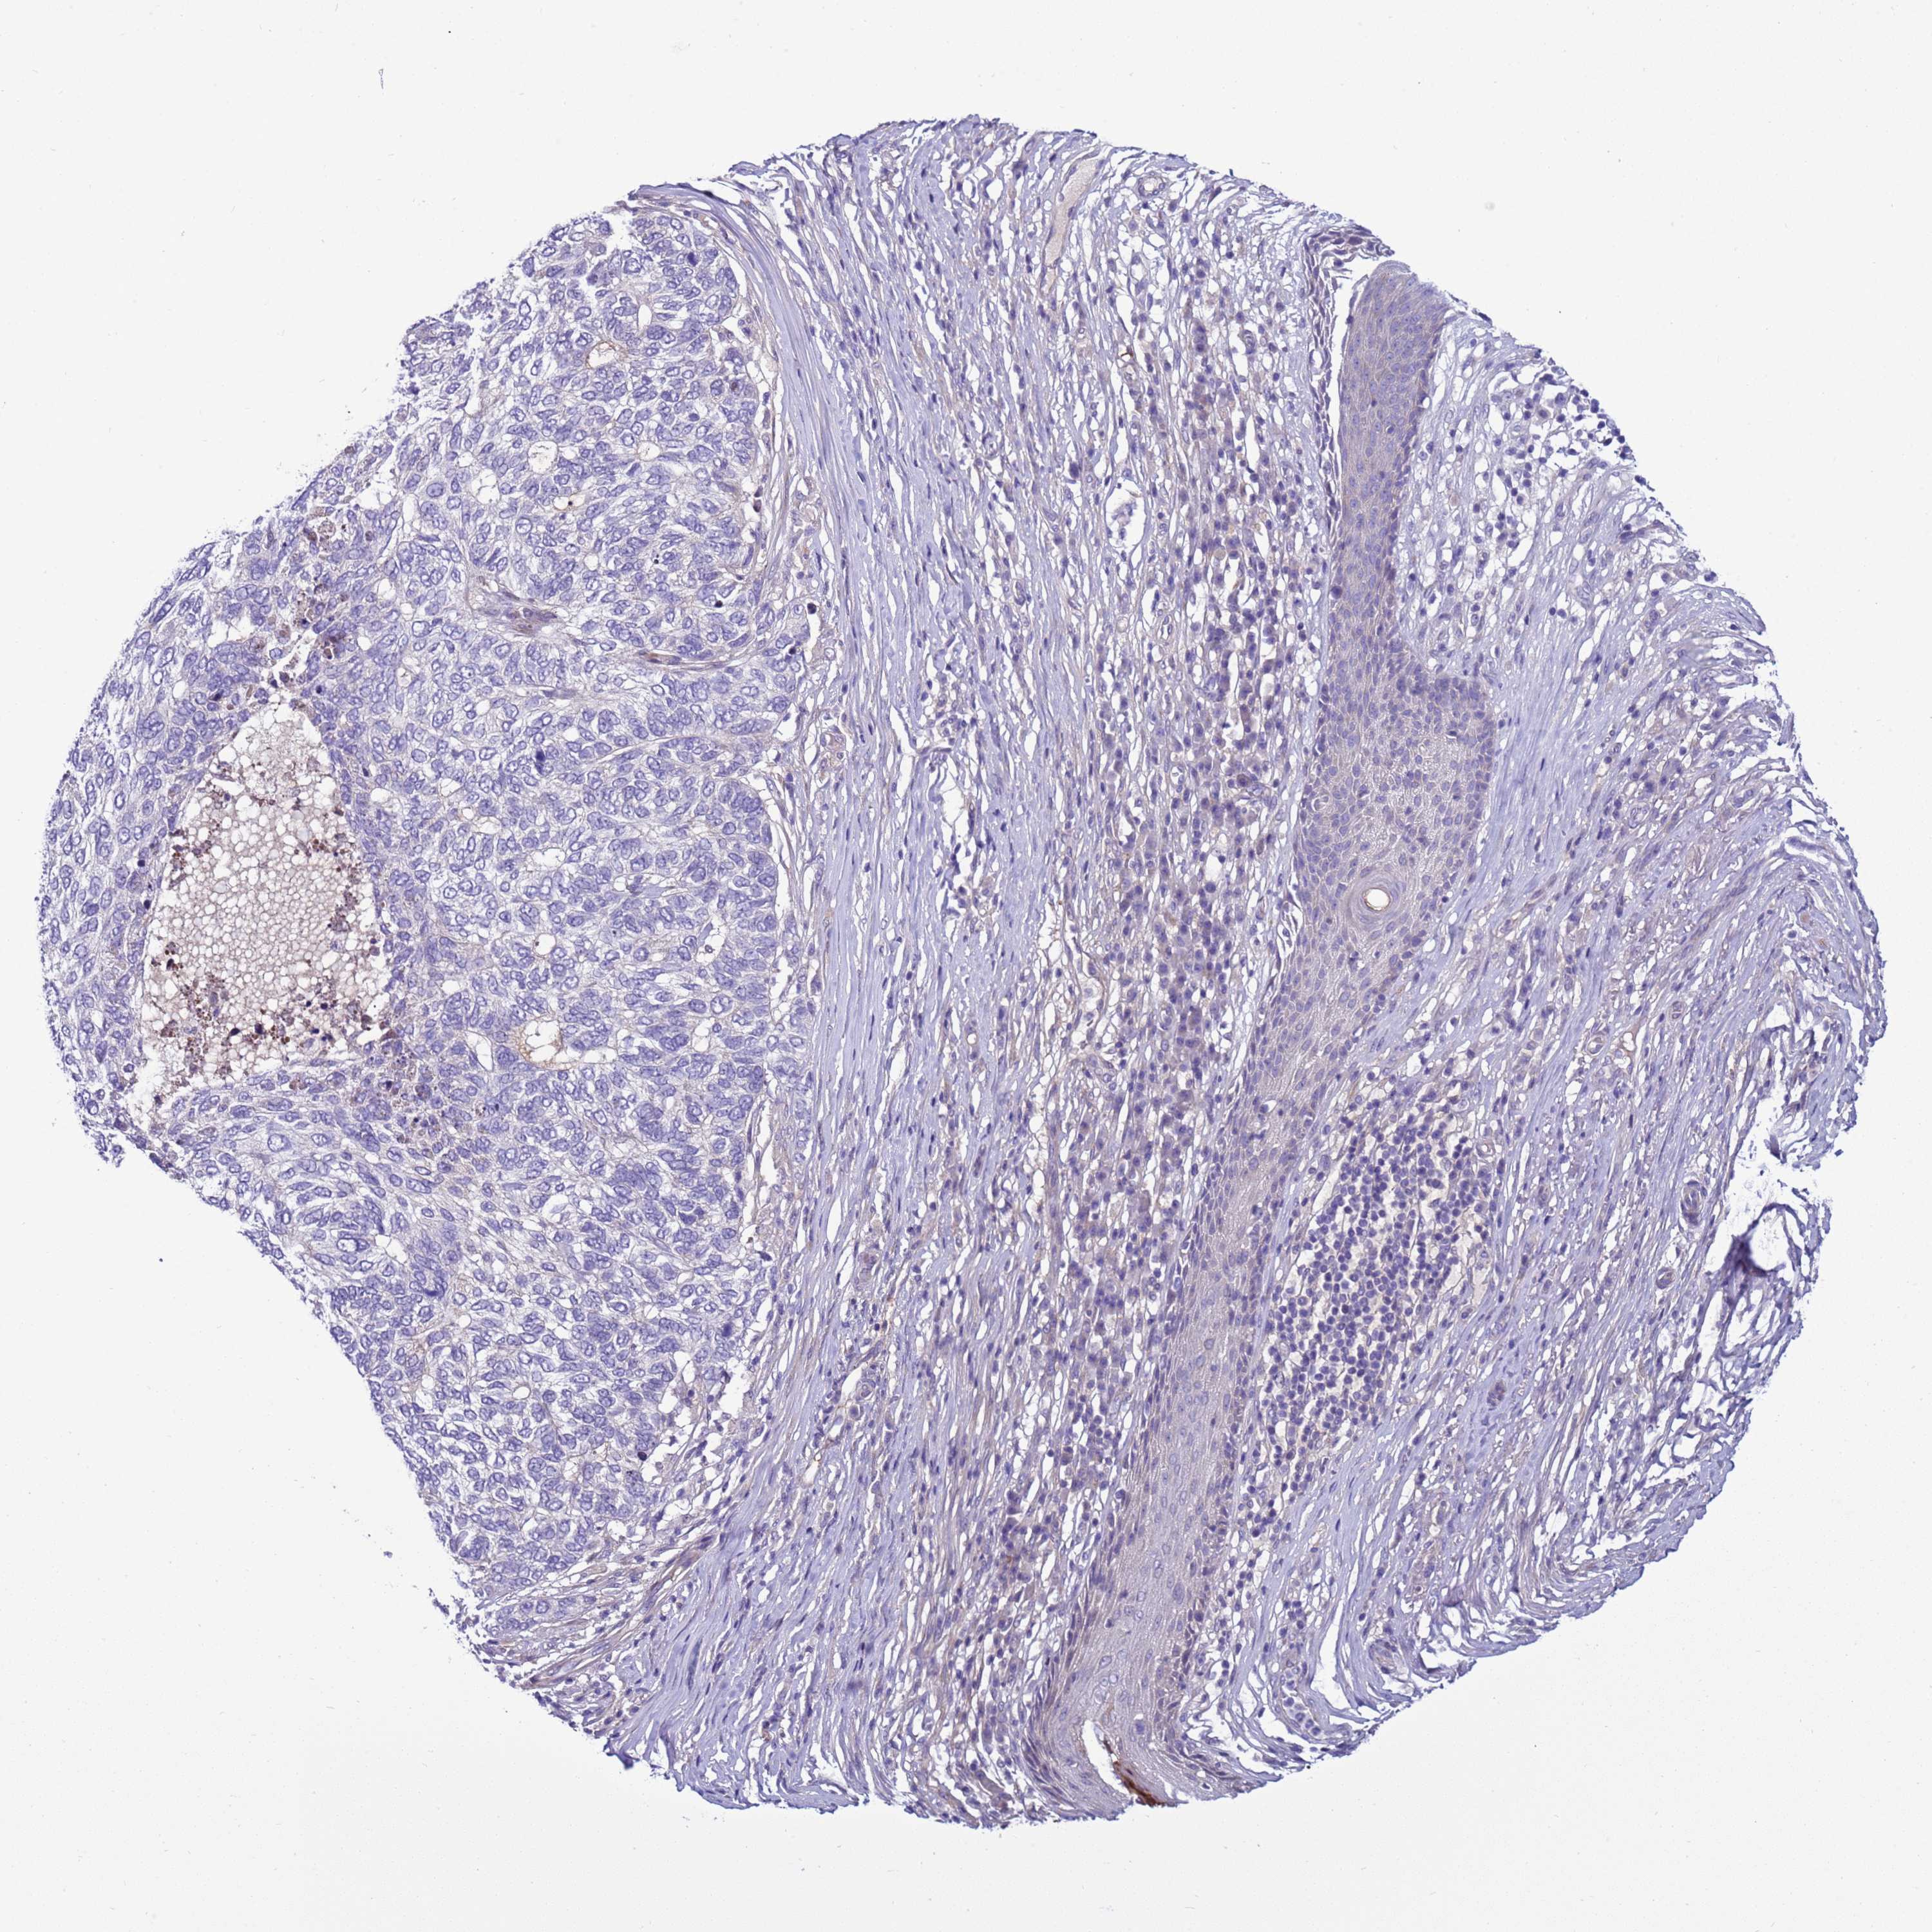

SKIN CANCER - Protein expressioni

A mouse-over function shows sample information and annotation data. Click on an image to view it in a full screen mode. Samples can be filtered based on level of antibody staining by selecting one or several of the following categories: high, medium, low and not detected. The assay and annotation is described here.

Antibody stainingi

Antibody staining in the annotated cell types in the current human tissue is reported as not detected, low, medium, or high, based on conventional immunohistochemistry profiling in selected tissues. This score is based on the combination of the staining intensity and fraction of stained cells.

Each image is clickable and will lead to virtual microscopy that enables deeper exploration of all samples and also displays staining intensity scores, fraction scores and subcellular localization as well as patient and tissue information for each sample.

Antibody HPA043704

Squamous cell carcinoma, NOS